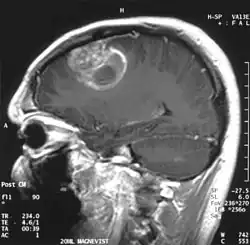

Глиобластома

Мультиформная глиобласто́ма (англ. Glioblastoma multiforme, GBM) — наиболее частая и наиболее агрессивная форма опухоли мозга, которая составляет до 52 % первичных опухолей мозга и до 20 % всех внутричерепных опухолей. Несмотря на то, что глиобластома является наиболее частой первичной опухолью мозга, на 100 000 жителей Европы и Северной Америки регистрируется всего 2—3 случая заболевания[1]. Термин «глиобластома» подразумевает два варианта этой болезни: гигантоклеточная глиобластома и глиосаркома.